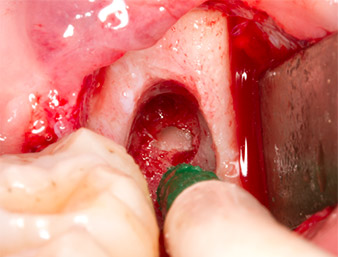

Dopo l'anestesia tronculare e l'anestesia locale, il sito operatorio è stato aperto e il tessuto molle esposto per l'accesso retromolare boccale (Fig. 3).

Il tessuto al di sopra del residuo di radice non era completamente ossificato ed era costituito per la maggior parte da tessuto di granulazione modificato dall'infiammazione (Fig. 4).